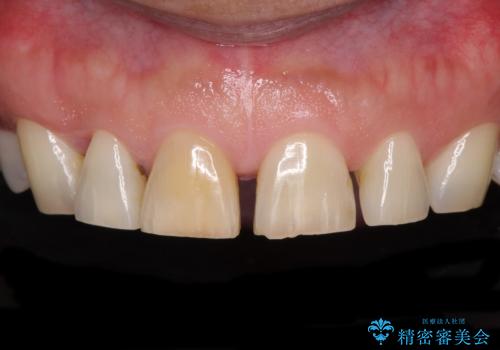

- 前歯の目立つ隙間を気にして来院された患者様です。

高校生の頃に矯正治療を行ったものの、強い咬合力により上顎が拡大され、正中に隙間ができてしまいました。

通常では歯の周囲全体を削った上でクラウンを装着することが多いのですが、咬合力が非常に強く、クラウンではセラミックが欠けてしまう可能性が考えられたため、咬合を変えることとのないラミネートベニアにて治療を行うこととしました。